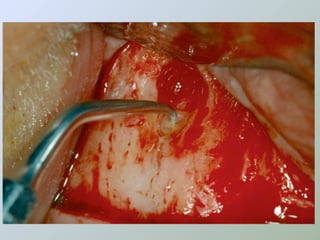

Acesso ao

Acesso ao periápice

• Freqüentemente o

osso cortical sobre o

ápice é reabsorvido

expondo uma lesão de

tecido mole

• Ampliar a abertura óssea

• Cinzel

• Broca esférica cirúrgica

• Expor a raiz e boa parte da

lesão

• Irrigação abundante

• Solução fisiológica

• Exposição óssea suficiente

para permitir boa visualização